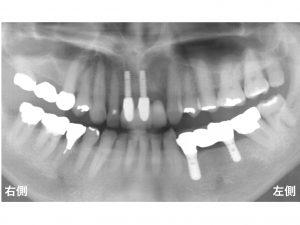

その時のレントゲンが以下です。

仮歯を装着してあります。